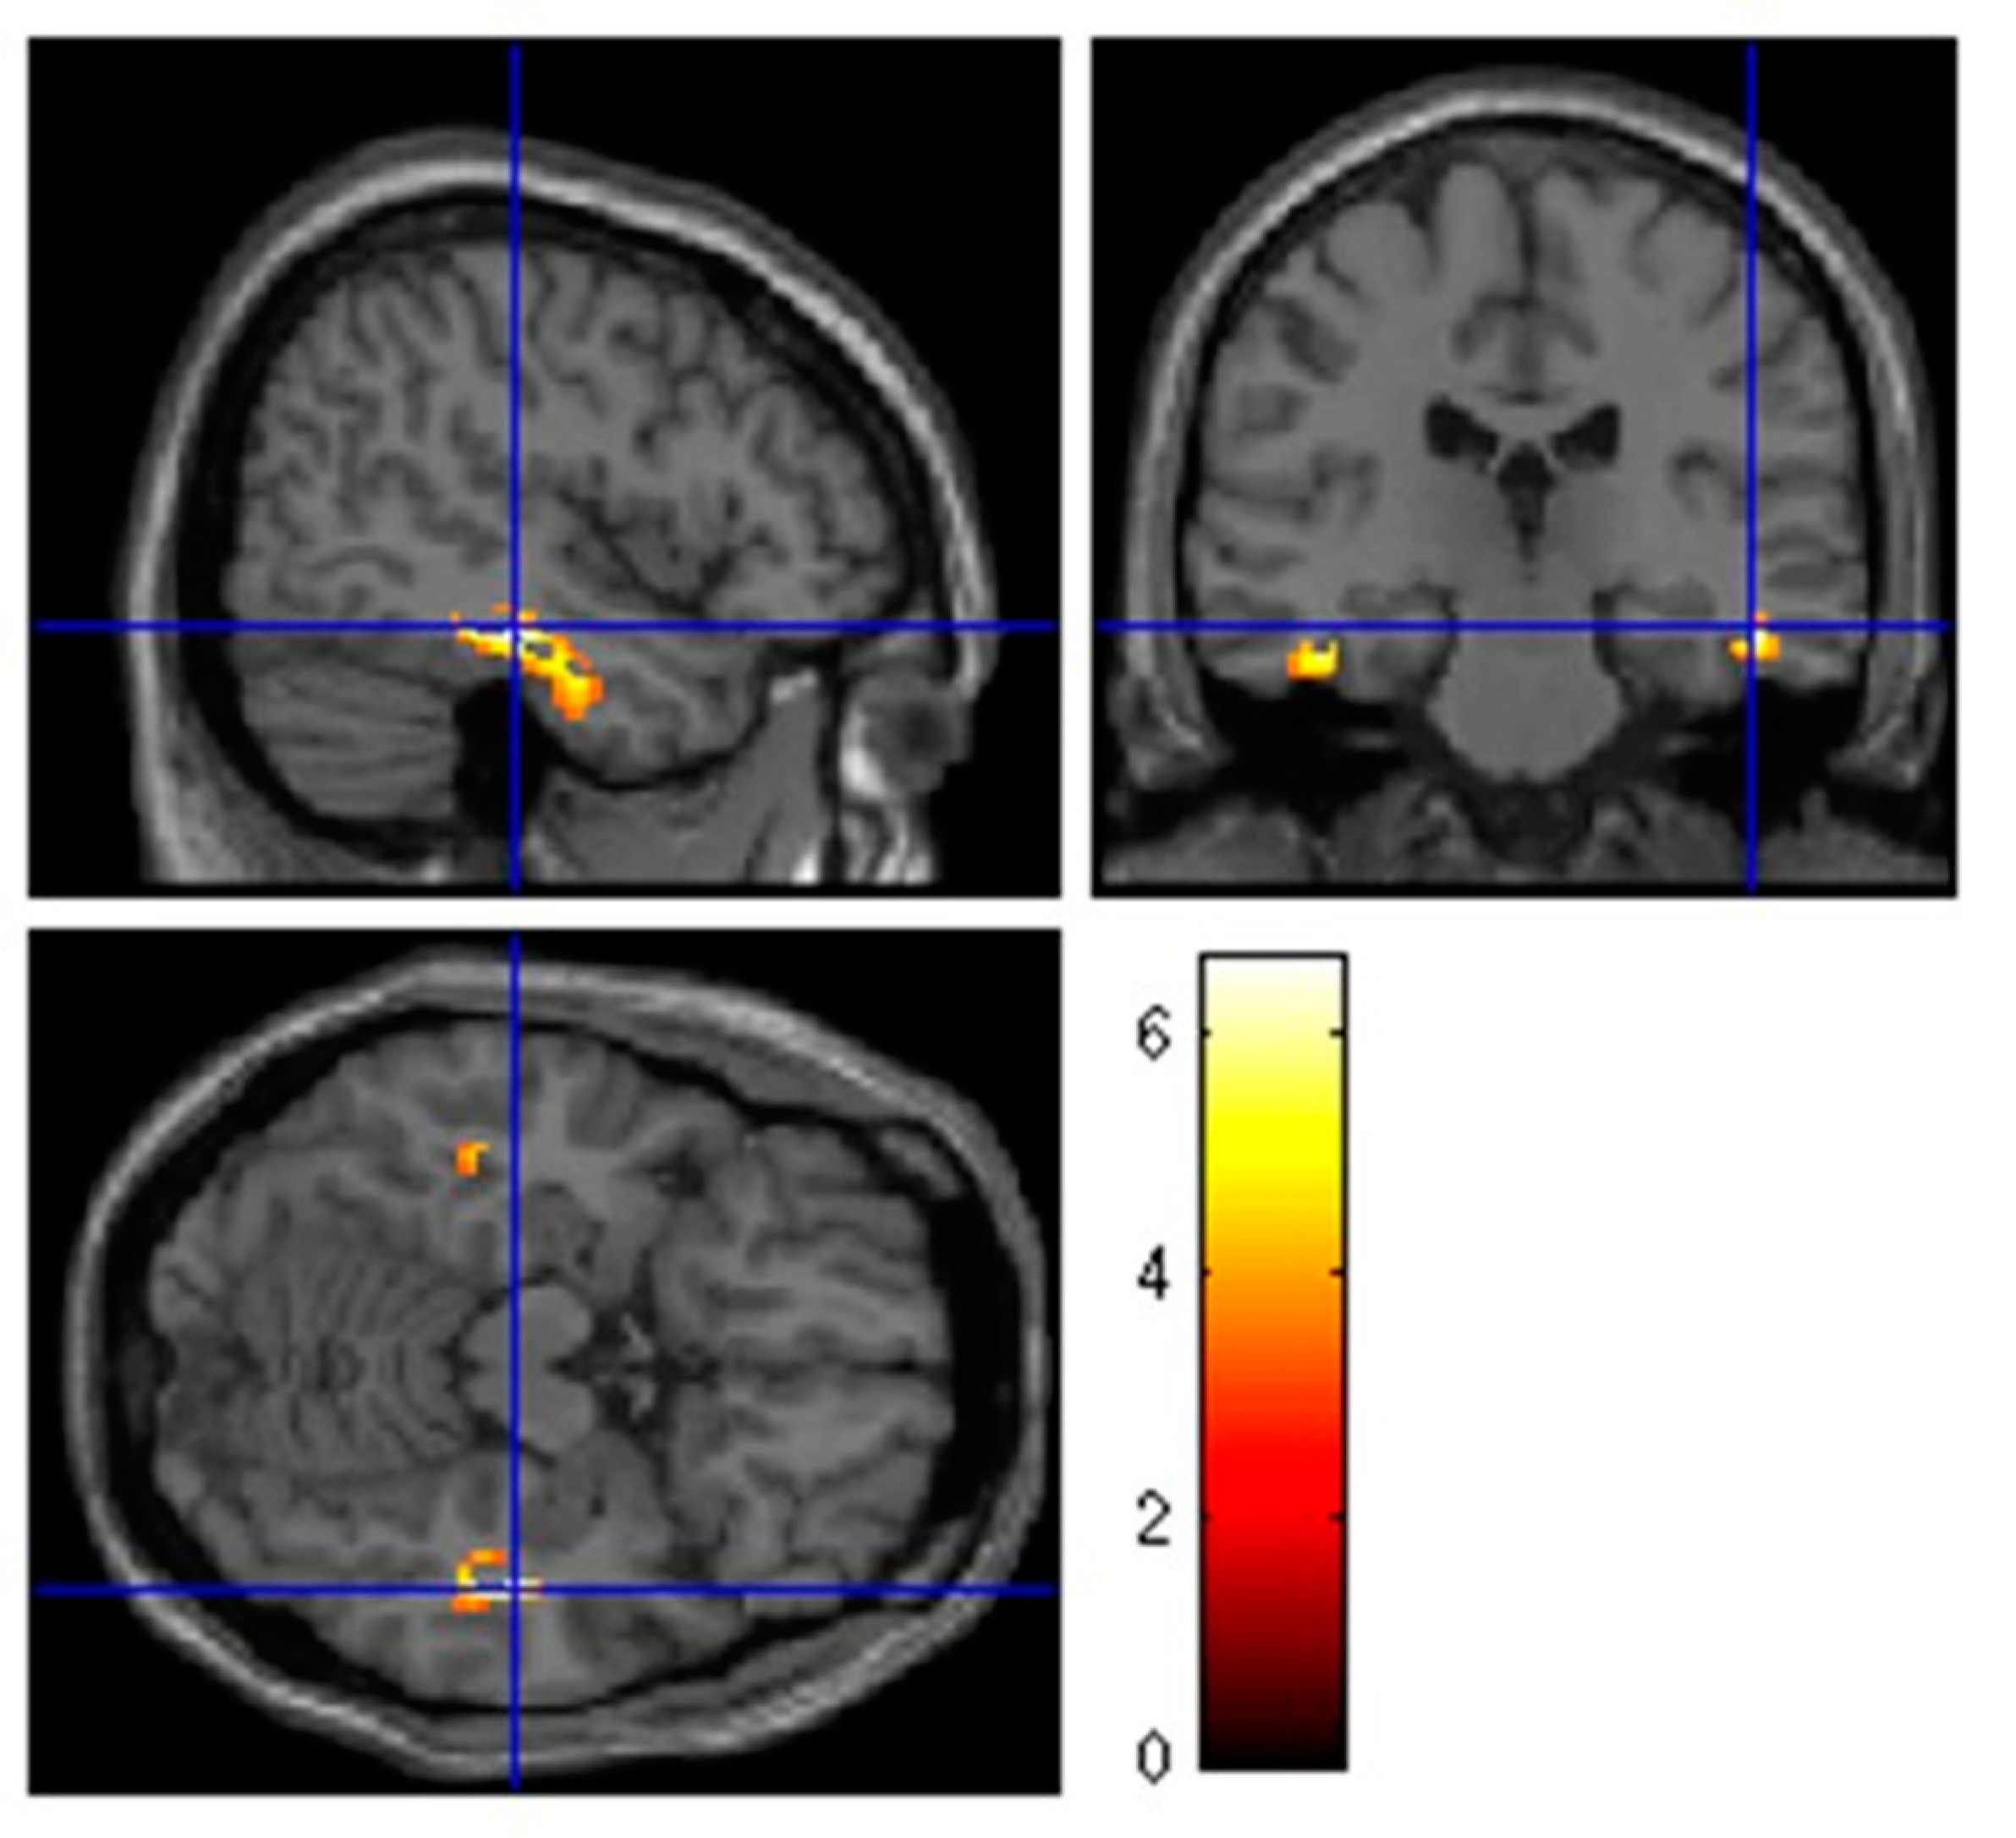

| Cluster Level | Peak Level | |||||||

|---|---|---|---|---|---|---|---|---|

| Cluster Extent | Corrected p-Value | Cortical Region | Maximum Zscore | Talairach Coordinates | Cortical Region | BA | ||

| 260 | 0.032 | |||||||

| R-limbic | 5.68 | 45 | −26 | −9 | Parahippocampal Gyrus | 36 | ||

| R-Temporal | 3.45 | 45 | −22 | −11 | Fusiform Gyrus | 20 | ||

| R-Temporal | 3.41 | 45 | −33 | −9 | Fusiform Gyrus | 37 | ||

| 155 | 0.034 | L-Limbic | 5.15 | −39 | −29 | −13 | Parahippocampal Gyrus | 36 |

| L-sublobar | 3.36 | −44 | −37 | 17 | Insula | 13 |